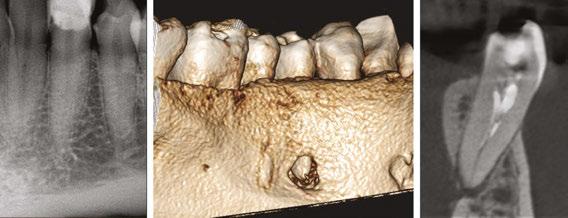

Figures 1A-1C: 1A. Preoperative X-ray. 1B. Immediate postoperative X-ray. 1C. Follow-up after 9 years and 10 months

Of the total, 29 had long-term radiographic follow-ups that ranged from a minimum of 6 months to a maximum of 25 years, with an average of 5 years, 4 months. Of the cases with radiographic follow-ups, 28 were considered successful and one failure (Table 2). Of the successful cases, 17 corresponded to treatments and 11 to retreatments (Figures 1A, 1B, 1C, and 2A, 2B, 2C). The tooth considered failed was a retreatment.

IRR is a disease of the dental pulp that affects the dentin wall, which is reabsorbed by clastic action. It can occur in any tooth, although its presence is more frequent in those more susceptible to different kind of trauma. According to what was observed in this study, the upper incisors and the lower first molars are the most likely to present IRR, and this could be since the former are the ones that often suffer traumatic injuries, while the lower molars suffer more the action of orthodontic forces (Figures 3A, 3B, 3C).

The radiographic appearances that generates the IRR are varied. The most common one observed in the present study was a circular shape with regular and symmetrical walls specially in single-rooted teeth (Figure 4A), although there were also some

Figures 2A-2C: 2A. Preoperative X-ray. 2B. Immediate postoperative X-ray. 2C. Follow-up after 18 years and 6 months

Figures 3A-3C: 3A. Preoperative X-ray. 3B. Immediate postoperative X-ray. 3C. Follow-up after 4 years

irregular ones with asymmetrical walls (Figure 4B). In molars, when resorption affects the pulp chamber, it was commonly seen as an irregularly shaped radiolucent cavity2 (Figure 4C).

Figure 4A-4C: 4A. Maxillary lateral incisor with an internal resorption at the coronal third. 4B. Mandibular canine with an internal resorption in the middle-apical area. 4C. Mandibular molar with an irregular internal resorption in the coronal portion Figures 5A-5C:

5A. Preoperative X-ray. 5B. Immediate postoperative X-ray. 5C. Follow-up after 1 year and 9 months EP